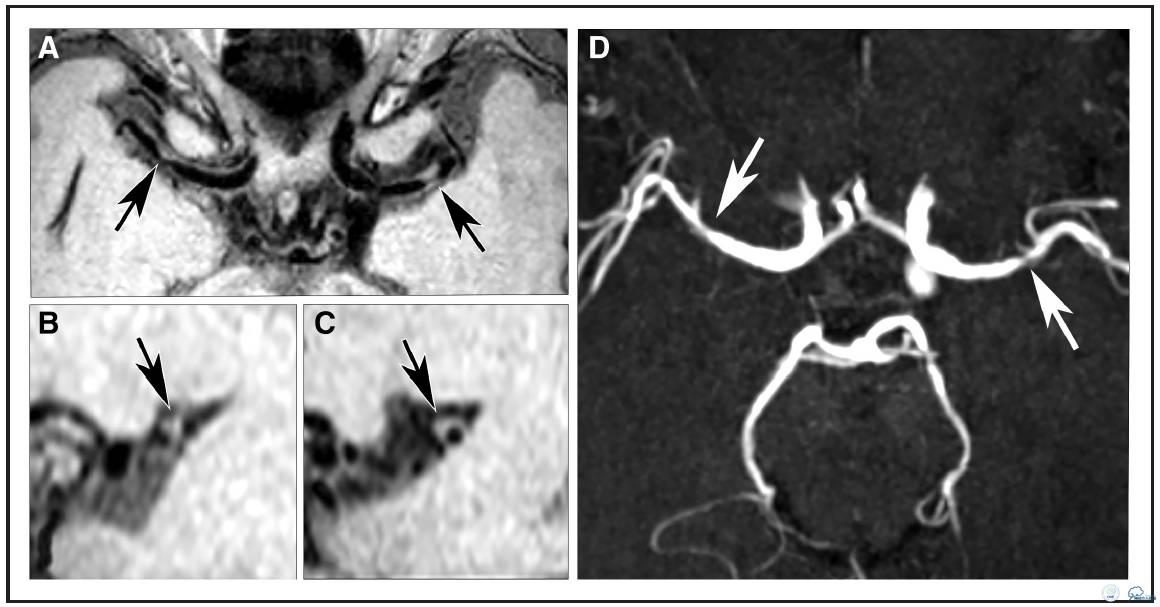

图2:78岁TIA女性患者。A:等中心重建容积采集T1加权快速自旋回波序列成像发现右侧大脑中动脉双侧局部血管壁病变(箭头A),矢状位重建图像(B)右侧大脑中动脉病变(C)显示双侧病变均为偏心性。D:横断面时间飞跃法磁共振血管造影显示对应位置症状性左侧MCA狭窄,无症状性右侧MCA不规则狭窄(箭头D)。

分布、负荷和特征